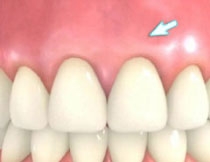

| 歯周病が進行したケースでは盲目下でポケット内の歯石を確実に除去するには限界があります。 | 局所麻酔をした後、歯茎を切開し、明視下にて歯根面の歯石や炎症組織を取り除き、歯周ポケットの除去をおこないました。 |